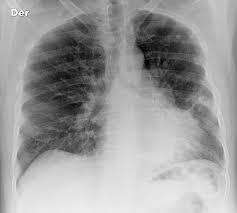

Pain in the affected bone is the most common sign of bone cancer. Bone metastasis can occur in any bone but more commonly occurs in the spine, pelvis and thigh. Joint swelling and stiffness which may be the result of a tumor located near or in the joint a lump in the back of the throat if there is cancer in the bones of the neck. Bone cancer is rare, making up less than 1 percent of all cancers. Bone pain is the most common symptom of metastatic bone cancer.

When cancer is detected in bones, it either originated in. Pelvic pain or bone pain; Signs of anemia are tiredness, weakness, and shortness of breath. It may be worse at night or when the bone is used, for instance, leg pain when walking. Surgical removal of the cancer may be considered for pelvic cancer patients. Know the signs and symptoms of bone cancer. If you notice any of these symptoms, see your doctor. Bone metastasis may be the first sign that you have cancer, or bone metastasis may occur years after cancer treatment. Bone pain can cause a dull or deep ache in a bone or bone region (e.g., back, pelvis, legs, ribs, arms). Any bone can be affected, although bone cancer most often develops in the long bones of the legs or upper arms. One of the most common pelvic cancer symptoms is pelvic pain. Back pain is a widespread issue for adults, and this can delay a diagnosis of pelvic bone cancer. Depending how severe the cancer is it can require either chemotherapy or the removal of the bladder.

Bone metastasis can occur in any bone but more commonly occurs in the spine, pelvis and thigh. Sometimes, people with bone sarcoma do not have any of these changes. This type of cancer is rare, with only around 550 cases each year 2. In contrast, some other metastatic tumors, such as those from the prostate, are commonly osteoblastic, meaning that they form new bone and increase the brittleness of the bones. Pelvic pain or bone pain;